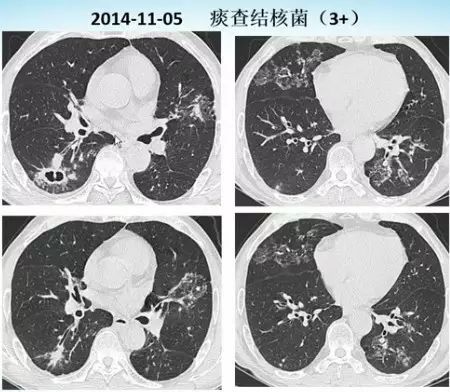

肺内“烟花征”,为活动性肺结核的CT表现之一。是结核经支气管播散并由多发小叶中央结节堆积而成,形态特征似烟花在空中散开。病理基础为细支气管及肺泡内干酪坏死性肉芽肿。